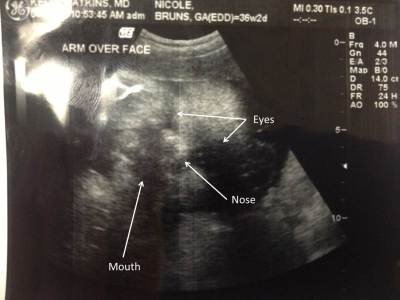

While I had a sono, it’s tough to see this guy. The sonographer commented that he doesn’t have much room. In the picture, you really have to use your imagination. I tried to help you out. She did say they saw fuzzy little hair on his head!